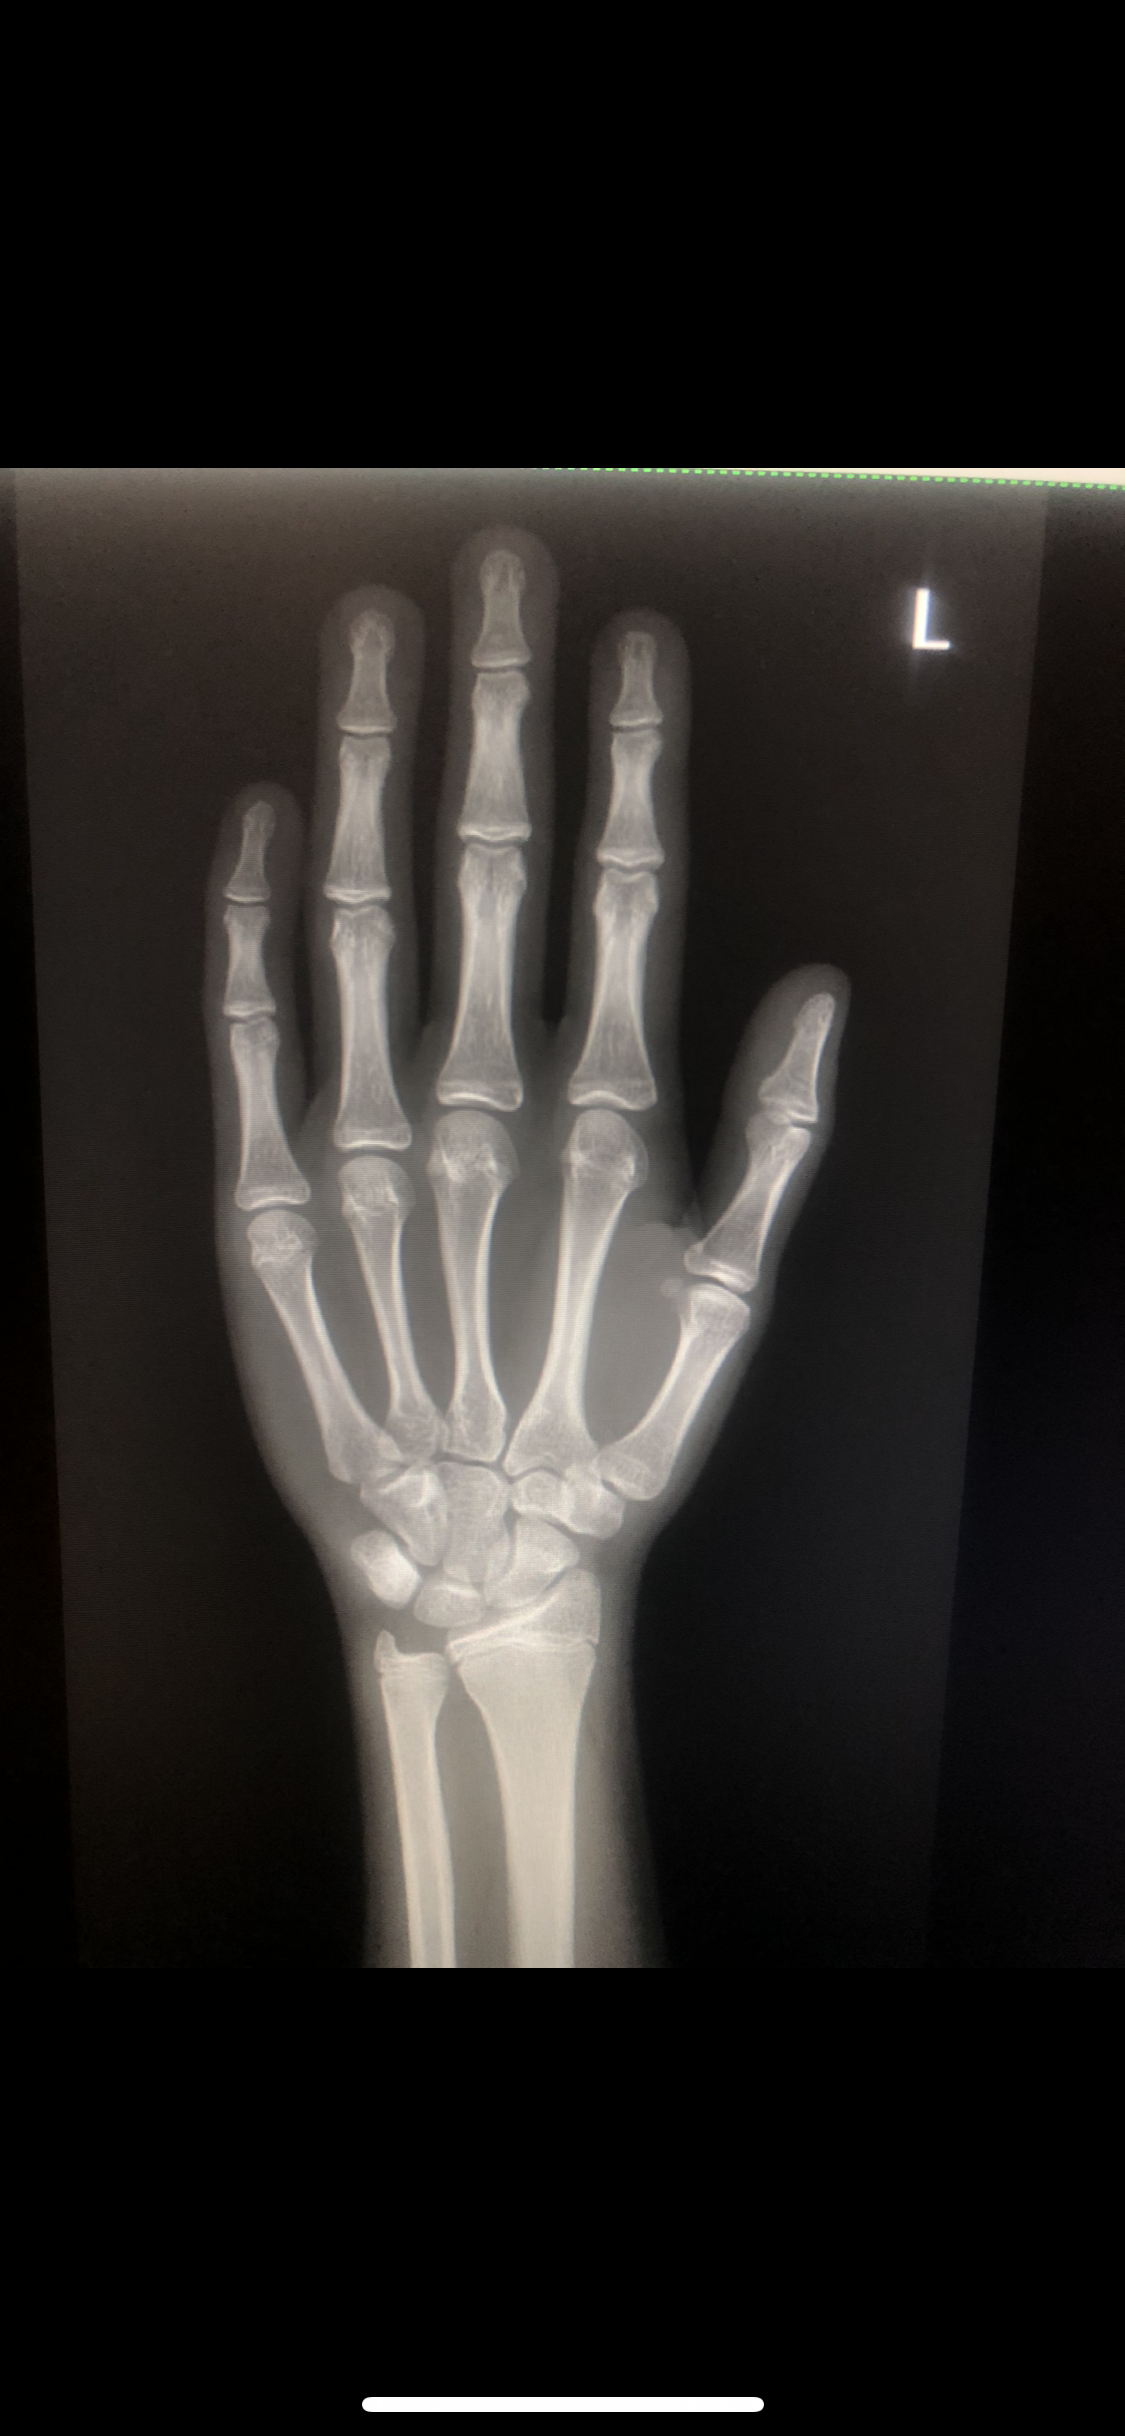

I have been diganosed ghd at a time where my g plates are almost fusing in that stage and i told my doctor abt it he said u have come too late i wouldve given u ai if u have came at 14 and said wont prescribe u now its gona ruin the gh ur ok rn nad bla bla:feelsrope::feelsrope::feelsrope::feelsrope::feelsrope::feelsrope::feelsrope: should i get ai myself or its pointless

Attachments

• IMG_2301.png

IMG_2301.png

I have been diganosed ghd at a time where my g plates are almost fusing in that stage and i told my doctor abt it he said u have come too late i wouldve given u ai if u have came at 14 and said wont prescribe u now its gona ruin the gh ur ok rn nad bla bla:feelsrope::feelsrope::feelsrope::feelsrope::feelsrope::feelsrope::feelsrope: should i get ai myself or its pointlessView attachment 4953277